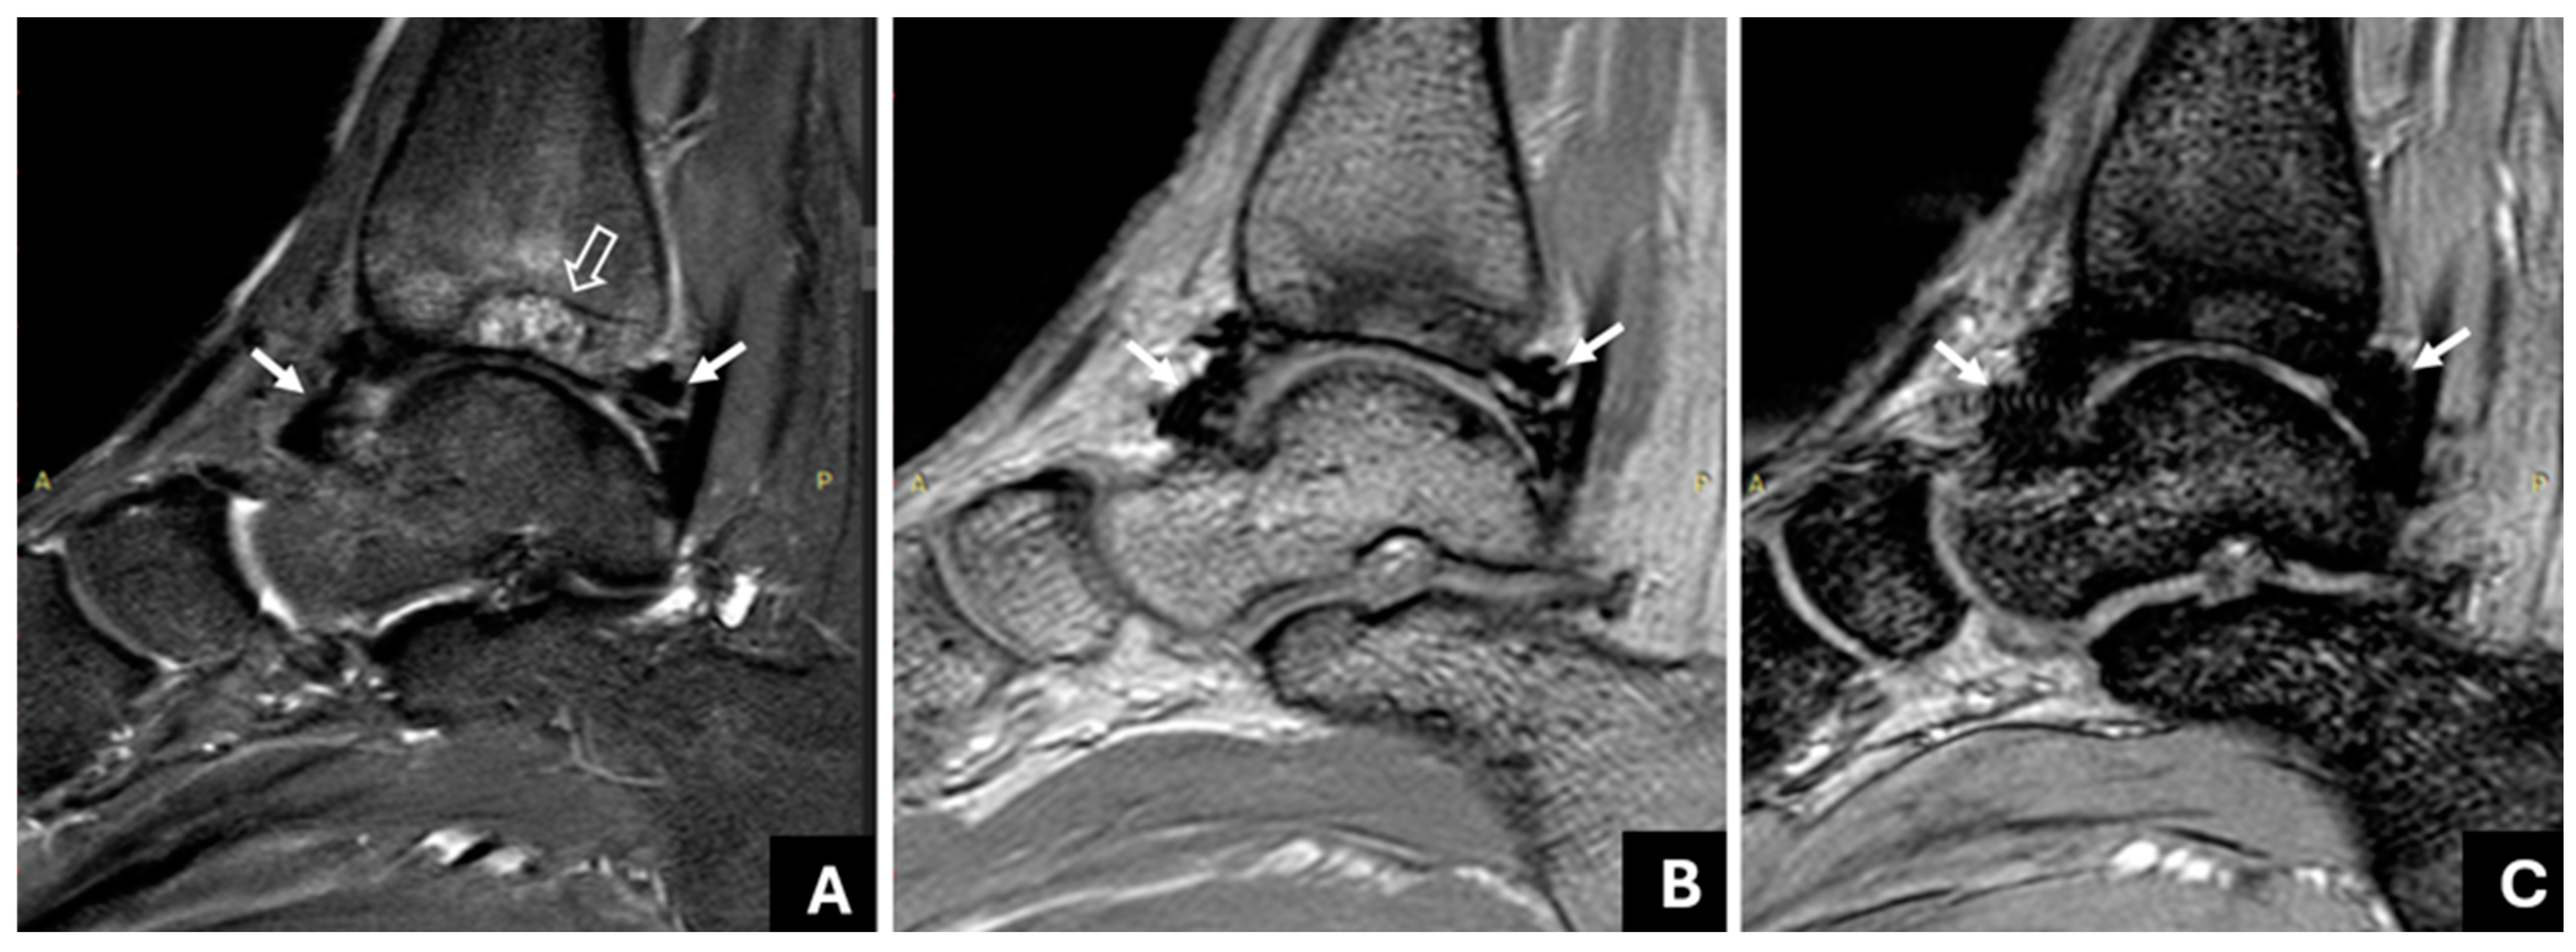

3.2. The Association of Joint Hemosiderin Deposition with Synovial Thickening, Effusion, and Osteochondral Changes (OCC)

3.3. Association of Joint Hemosiderin Deposition with the Number and Chronicity of Joint Bleeds and Clinical Score